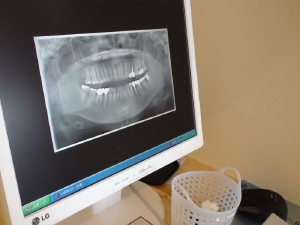

虫歯治療

現在お痛みのある方はもちろん、定期検診をご希望の方、つめものやかぶせものも多種多様なものを揃え、じっくりとご希望を聞きながら治療をしていきます。また、歯科が苦手という方のために最新の器械を取り揃え、常に「痛くない麻酔」を心がけております。

最新の治療(ドッグスベストセメントを使った虫歯治療、3mix治療など)を常に取り入れております。治療に関することなど、何でもお気軽にご相談ください。